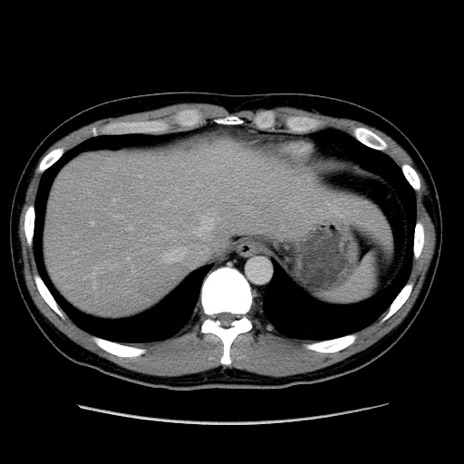

症例4(横断像)

【症例】30歳代男性

【主訴】腹痛、嘔吐

【現病歴】昨晩から突然の腹痛あり、その後嘔吐、軟便も出現。腹痛が改善しないため救急搬送となる。2日前にしめ鯖の食事歴あり。

【身体所見】意識清明、苦悶様、BP 135/90mmHg、BT 35.7℃、腹部:平坦、やや硬、心窩部〜臍部に自発痛、圧痛あり、筋性防御+、反跳痛-

【データ】WBC 8100、CRP 0.57